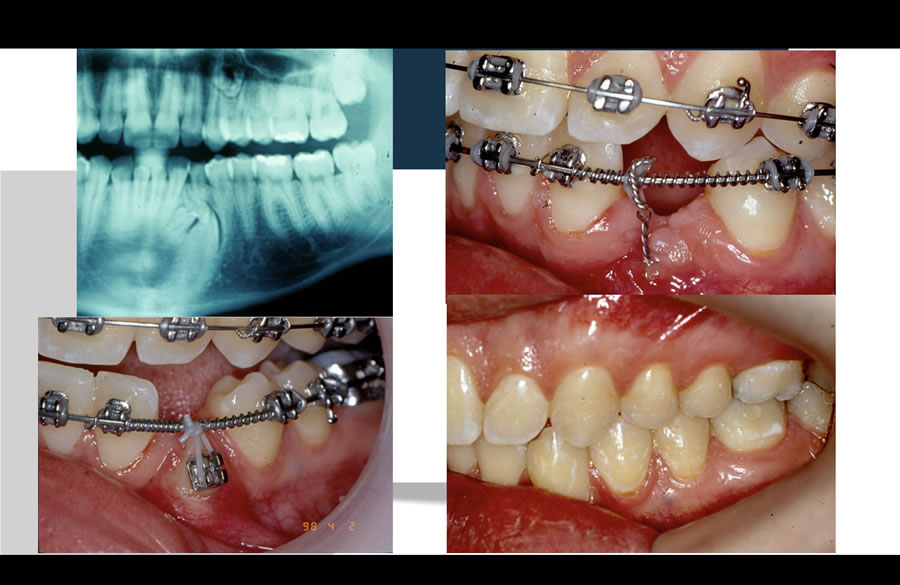

Nesses casos, faz-se necessário um exame radiográfico detalhado dos ossos para avaliar a posição exata do dente. Em alguns casos, pode ser necessário, até mesmo, a utilização da tomografia computadorizada.

Normalmente, o paciente fica inicialmente em torno de 1 ano com o aparelho fixo a fim de fazer o alinhamento inicial.

Após essa fase, faz-se uma exposição cirurgia do dente com um cirurgião Bucomaxilofacial, onde um acessório (botão metálico) é colado no dente a fim de permitir o seu tracionamento. O tempo para o tracionamento do dente é imprevisível e pode durar no mínimo 6 meses. Após o tracionamento, segue-se o tratamento ortodôntico a fim de acertar a oclusão (mordida) e o alinhamento dos dentes.